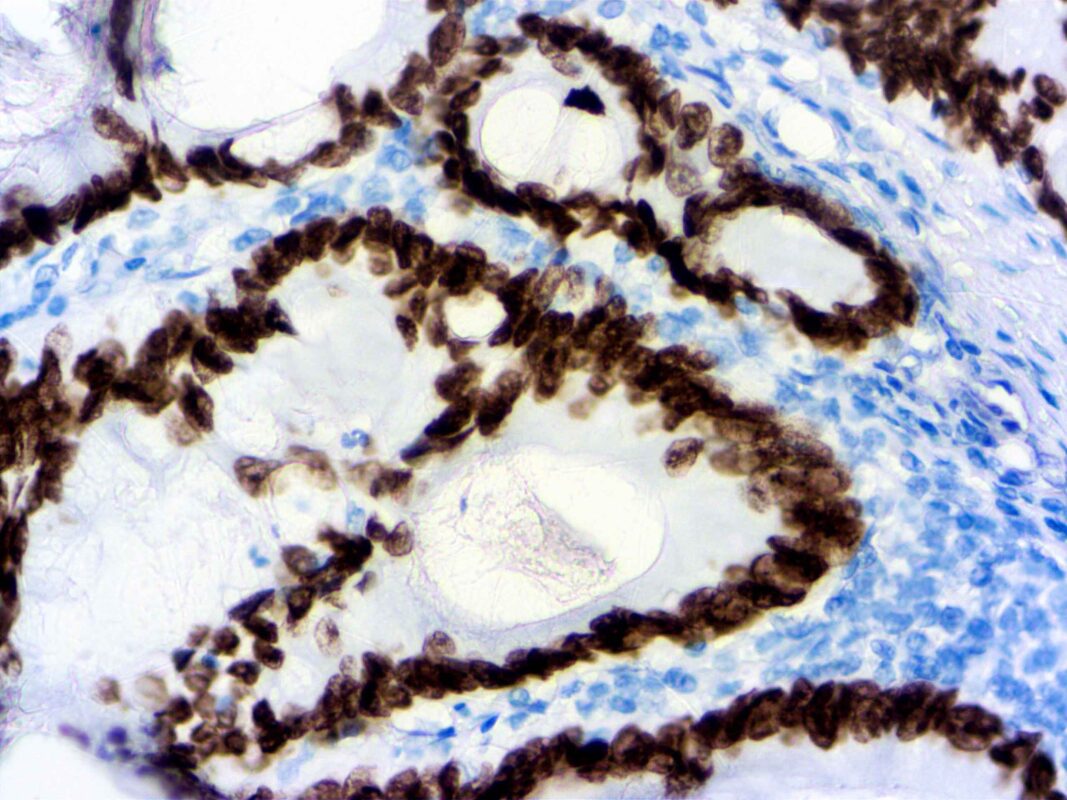

formalin fixed paraffin embedded human Colon Ca stained with SATB2 40x Published December 6, 2021 at 2560 × 1920 in formalin fixed paraffin embedded human Colon Ca stained with SATB2 40x formalin fixed paraffin embedded human Colon Ca stained with SATB2 40x formalin fixed paraffin embedded human Colon Ca stained with SATB2 40x ← Previous Next →